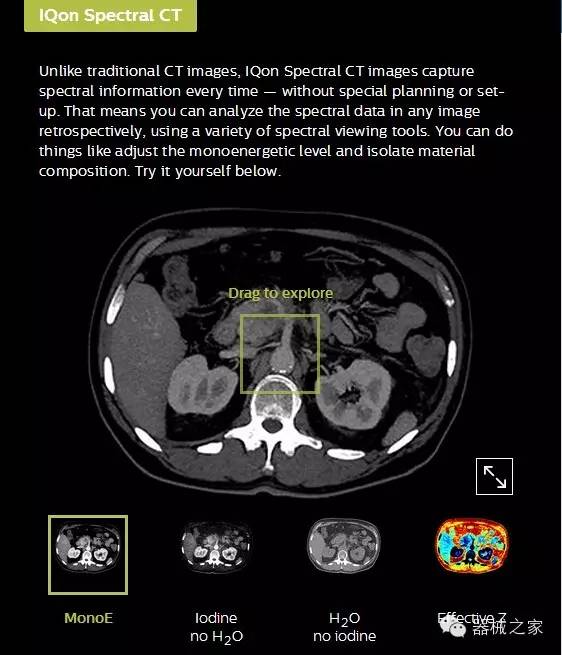

IQon光譜CT能夠按照需求提供光譜量化和工具,并能通過簡單工作流程、在低劑量下對結(jié)構(gòu)進行定性分析

IQon光譜CT -- 是業(yè)界首臺以探測器為成像基礎(chǔ)的光譜CT,它可以在單次常規(guī)掃描下獲得傳統(tǒng)解剖影像及光譜功能影像。不僅可以提供精準的診斷信息,還可簡化工作流程、在低劑量下完成定量與定性分析。